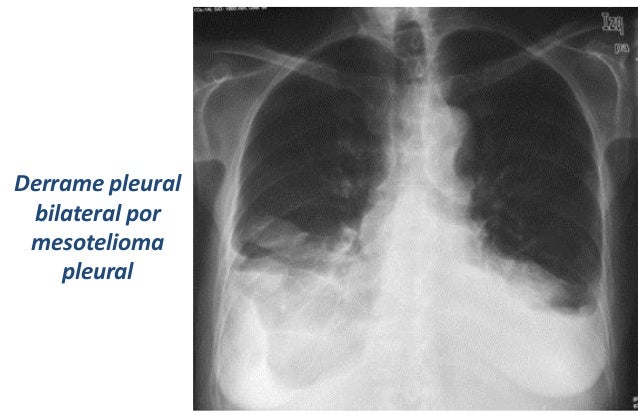

Mesotelioma liquido pleural image results. More mesotelioma liquido pleural images. Aspectos diagnÓsticos y terapÉuticos en el mesotelioma. Se distinguen los tipos epitelioide, sarcomatoso y bifásico en el mesotelioma pleural maligno, pero también hay raros subtipos, como el mesotelioma desmoplásico (que se puede confundir con pleuritis fibrosa benigna), el mesotelioma de células pequeñas y el mesotelioma linfohistiocitoide (que podría confundirse con un linfoma), y los. Sintomas do mesotelioma. Tipos de mesotelioma existem diversos tipos de mesotelioma dependendo da sua localização dentro do corpo. Mesotelioma pleural os sintomas deste subtipo de mesotelioma são dor no peito, falta de ar, diminuição da expansibilidade torácica, sons de respiração fraco ou forte, tosse seca, chiados e derrames pleurais. ¿qué es el mesotelioma pleural? Mesotelioma mas. El mesotelioma pleural tiene los mismos síntomas que las condiciones respiratorias más comunes, como la neumonía o la enfermedad pulmonar obstructiva crónica (epoc). Bajo un microscopio, también es difícil para los médicos distinguir entre el mesotelioma pleural y otros tipos de cáncer. Mesotelioma maligno medlineplus enciclopedia médica. El mesotelioma maligno es un cáncer difícil de tratar. Por lo regular, no existe una cura, a menos que la enfermedad se detecte muy temprano y el tumor se pueda extirpar completamente con cirugía. La mayoría de las veces, al momento del diagnóstico, la enfermedad está demasiado avanzada para una cirugía. Noticias sobre coche eléctrico el espaÑol. Find the results you're looking for with guardengine!

Mesotelioma pleural maligno neumosur. El mesotelioma es un tumor derivado de las células mesoteliales. Aunque puede asentar en peritoneo, túnica vaginal y pericardio, el 80% de los casos tienen su origen en la pleura. La incidencia del mesotelioma pleural (mp) está aumentando en la mayoría de los países de europa y en los ee.Uu. (Actualmente, 2.200 casos por.

Mesotelioma pleural maligno neumosur. El mesotelioma es un tumor derivado de las células mesoteliales. Aunque puede asentar en peritoneo, túnica vaginal y pericardio, el 80% de los casos tienen su origen en la pleura. La incidencia del mesotelioma pleural (mp) está aumentando en la mayoría de los países de europa y en los ee.Uu. (Actualmente, 2.200 casos por. Descubre nuestras pruebas de coches y encuentra el coche. Con el eniro, kia muestra que va en serio por el camino de la electromovilidad. A su versátil y práctico crossover, le configura con dos motores cien por cien eléctricos, con. Mesotelioma síntomas y causas mayo clinic. En general, el mesotelioma afecta el tejido que rodea los pulmones (pleura). Este tipo se denomina mesotelioma pleural. Otros tipos menos frecuentes de mesotelioma afectan el tejido del abdomen (mesotelioma peritoneal), el tejido que está alrededor del corazón y el que recubre los testículos. Atención del mesotelioma en mayo clinic. Golf costa adeje tarifas. Utilizamos cookies propias y de terceros para realizar análisis de uso y de medición de nuestra web para mejorar nuestros servicios. Si continua navegando, consideramos que acepta su uso. Tratamiento del mesotelioma maligno (pdq®)versión para. El mesotelioma maligno es una enfermedad por la que se forman células malignas (cancerosas) en el revestimiento del tórax o el abdomen. La exposición al amianto (asbesto) influye en el riesgo de mesotelioma maligno. Los signos y síntomas de mesotelioma maligno incluyen dificultad para respirar y. Mesotelioma wikipedia, la enciclopedia libre. Mesotelioma (o mesotelioma maligno) es una forma rara de cáncer que se desarrolla a partir de células transformadas originarias del mesotelio, el revestimiento protector que cubre muchos de los órganos internos del cuerpo. El mesotelioma pleural es una placa dura, blanquecina grisacea. Los diez coches eléctricos con más autonomía del mercado. Everymanbusiness has been visited by 1m+ users in the past month. Coche electrico coche electrico socialscour. Saber el consumo de combustible que hace nuestro coche es importante para hacer una conducción eficiente y notarlo en nuestra economía. Ada funes 13.03.2019 1323 h. El extraño caso del opel.